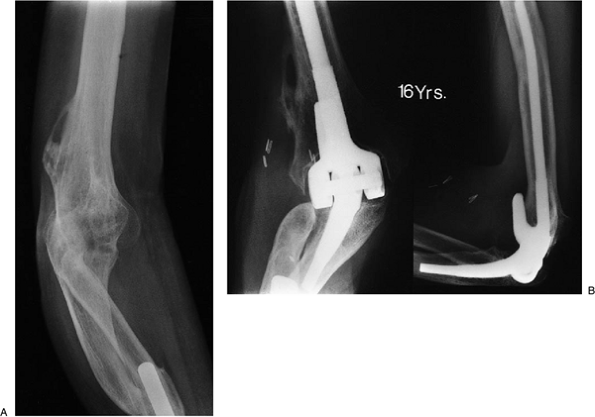

triceps from the olecranon is essential. An aggressive transection of

the fused joint or release of joint adhesions is coupled with a very

aggressive release of the anterior capsule and release of the collateral ligaments and release

of the flexor/extensor attachments to the humerus (Fig. 18-43). Additional steps to improve extension include the more proximal palcement of the humeral component (Fig. 18-44).

Figure 18-50. Severe deformity, spontaneously fused elbow, and one-bone forearm (A). Patient continues to function well 16 years after replacement (B).